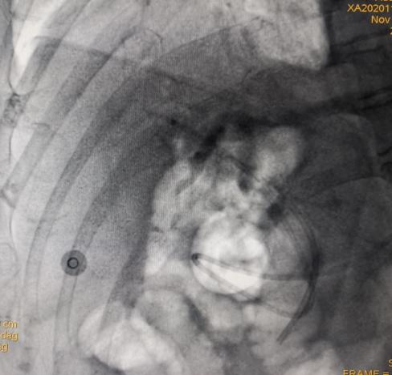

凭借扎实的ERCP专业功底和内镜操作技能,ERCP团队在短短20分钟就顺利完成了ERCP+EST+取石+ERBD+ENBD术,即胆总管造影、十二指肠乳头切开、胆总管末段嵌顿结石取出、胆总管支架植及鼻胆管引流术系列手术操作。

(ERCP术后胆管支架、鼻胆管X光线图片)